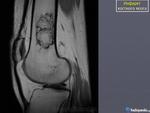

Женщина 1952 г.р.,направлена с диагнозом остеоартроз

Энхондрома, инфаркт кости, хондросаркома. Я в заключении такой бы диф. ряд написал.

На мой взгляд имеет место быть "Хрящевая матрица"

А с чего бы это костному мозгу обызвествляться? Больше не энхондрому похоже

+1.Энхондорма? Хондросаркома?? Для уточнения рекомендована КТ коленного сустава.

Значит, что имеются элементы хрящевой ткани. Есть вероятность наличия хрящевой опухоли.

Большое спасибо за комментарии!Сегодня пациентка принесла архивные снимки обоих коленных суставов,за 2008,2009,2011 года -картина такая же и на тех снимках,а на снимках правого коленного сустава за 2008 год такой же участок(немного меньших размеров) в области метадиафиза большеберцовой кости.Ни МРТ ни КТ никогда не делала.

Энхондрома все же не исключается.